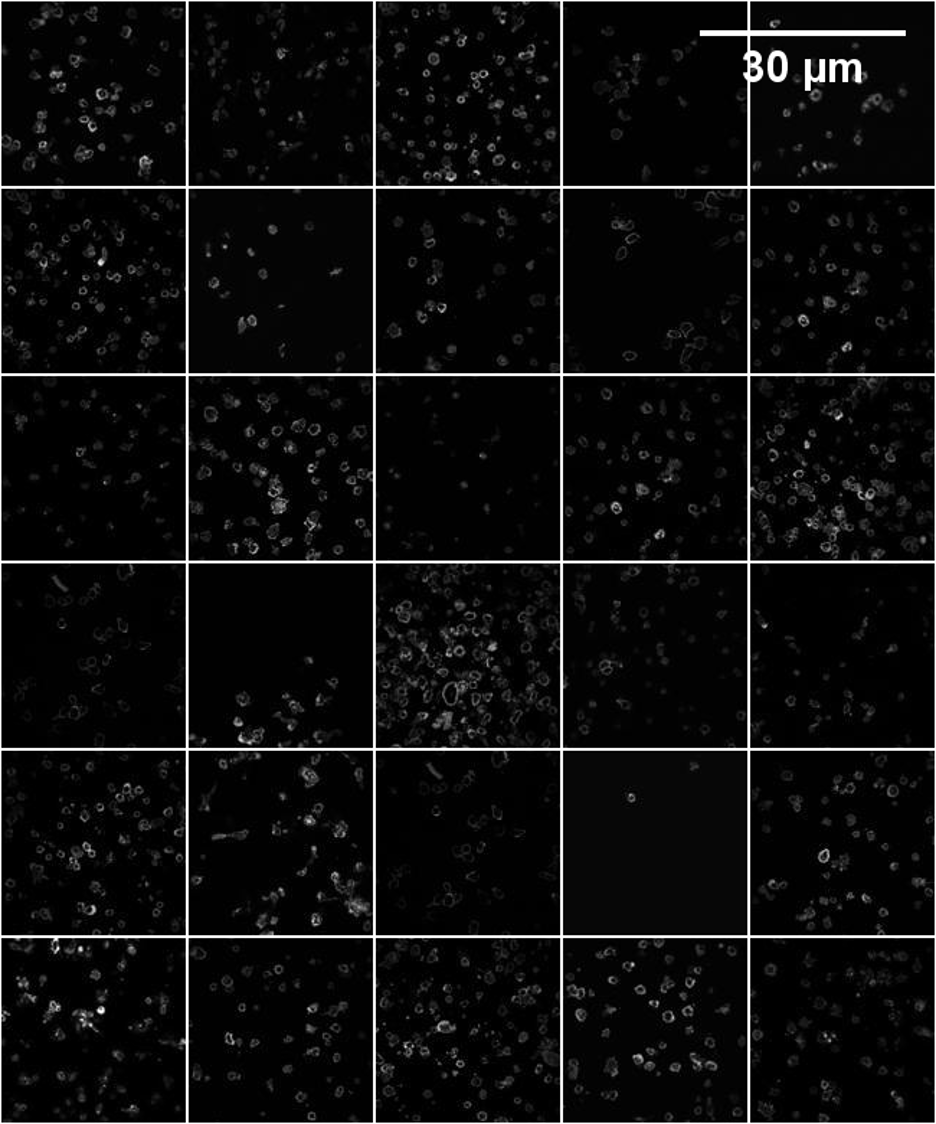

Figure S7: SCO real images on CAR-T/NK, Neural, and Kaggle datasets; the first two rows represent the SCO images and their masks from the CAR-T/NK dataset. The third and fourth rows represent the SCO images and their masks from the Neural dataset. The fifth and sixth rows represent the SCO images and their masks from the Kaggle dataset.

Refer to caption

Figure S8: SCO image generation on CAR-T/NK, Neural, and Kaggle datasets; the first two rows represent the SCO images and their masks from the CAR-T/NK dataset. The third and fourth rows represent the SCO images and their masks from the Neural dataset. The fifth and sixth rows represent the SCO images and their masks from the Kaggle dataset.

Figure S9: MCO real images on CAR-T/NK, Neural, and Kaggle datasets; the first two rows represent the MCO images and their masks from the CAR-T/NK dataset. The third and fourth rows represent the MCO images and their masks from the Neural dataset. The fifth and sixth rows represent the MCO images and their masks from the Kaggle dataset.

Figure S10: MCO image generation on CAR-T/NK, Neural, and Kaggle datasets; the first two rows represent the MCO images and their masks from the CAR-T/NK dataset. The third and fourth rows represent the MCO images and their masks from the Neural dataset. The fifth and sixth rows represent the MCO images and their masks from the Kaggle dataset.